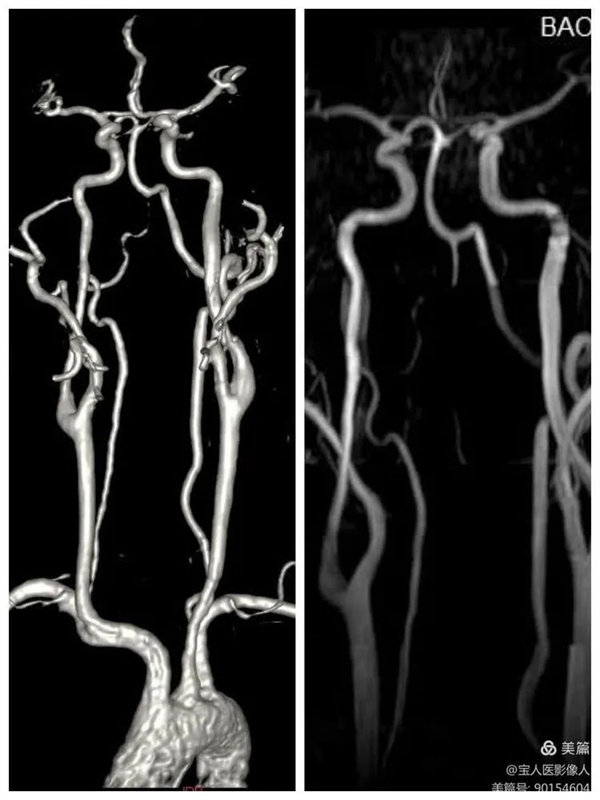

01、头颈部血管增强磁共振成像(CE-MRA)和血管壁成像(HR-VWI)

48岁的一名男性患者因长期头痛行颅脑MRI检查,有病变提示,遂进一步行头颈部血管增强磁共振成像(CE-MRA)和血管壁成像(HR-VWI),诊断为颈内动脉颅外段壁间血肿。

CE-MRA完美显示管腔,右侧颈内动脉狭窄

患者行CE-MRA、HR-VWI检查能清晰显示头颈部血管腔、血管壁及脑实质,完美显示动脉瘤和评估动脉瘤稳定性。

CE-MRA显示颈部血管清晰

CE-MRA主要优势:

1.血管腔的显示比MRA技术更可靠;

2.出现血管狭窄的假象明显减少,狭窄的程度反映比较真实;

3.注射对比剂后血管可显示至4-5级,且血管信号明显增强;

4.一次注射对比剂可完成多部位动脉的显示;

5.动脉瘤不易遗漏;

6.成像速度快。